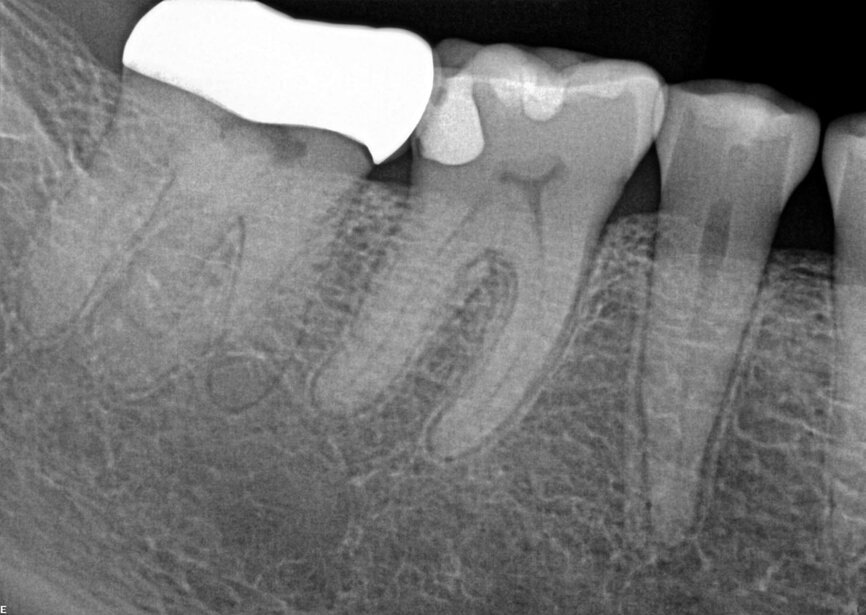

Fig. 17a: Case assisted with CBCT to determine anatomy pre-operatively. Note the multiple cross sections moving apically and the correlation to the 2-D view. Note also the conservative taper in relation to the root width. (Courtesy of Dr. Brett Gilbert)

Fig. 17b: Case assisted with CBCT to determine anatomy pre-operatively. Note the multiple cross sections moving apically and the correlation to the 2-D view. Note also the conservative taper in relation to the root width. (Courtesy of Dr. Brett Gilbert)

Fig. 17c: Case assisted with CBCT to determine anatomy pre-operatively. Note the multiple cross sections moving apically and the correlation to the 2-D view. Note also the conservative taper in relation to the root width. (Courtesy of Dr. Brett Gilbert)

Fig. 17d: Case assisted with CBCT to determine anatomy pre-operatively. Note the multiple cross sections moving apically and the correlation to the 2-D view. Note also the conservative taper in relation to the root width. (Courtesy of Dr. Brett Gilbert)

Fig. 17e: Case assisted with CBCT to determine anatomy pre-operatively. Note the multiple cross sections moving apically and the correlation to the 2-D view. Note also the conservative taper in relation to the root width. (Courtesy of Dr. Brett Gilbert)

Fig. 17f: Case assisted with CBCT to determine anatomy pre-operatively. Note the multiple cross sections moving apically and the correlation to the 2-D view. Note also the conservative taper in relation to the root width. (Courtesy of Dr. Brett Gilbert)

Managing complex anatomy is much simpler if the clinician has a pre-operative road map. The CBCT provides the roadmap and the surgical microscope the lens (literally) through which to visualize the result. Aside from a relaxed patient who is profoundly numb, being able to visualize anatomy by taking a pre-operative (and possibly intra-operative) CBCT and using a surgical microscope during treatment have no substitutes. They are the current “Gold Standard” in that 3-D imaging shows the clinician the true reality of a clinical situation as opposed to the suggestion gained from a 2-D radiograph. Proper interpretation of imaging prior to and/or during endodontic treatment goes a long way in taking the “guesswork” out of identifying canal location and other anatomical complexities as the procedure unfolds. In a 2014 study by El Fayad and Johnson, it was determined that when having a pre-operative CBCT as compared to 2-D radiographs alone, the treatment plan was modified 62 percent of the time. This is a huge game changer to think that the information learned from 3-D imaging changed the plan of treatment over six times out of 10 (Fig. 4).[2]